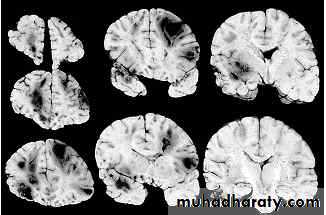

1. Diffuse Axonal Injury

Prolonged post-traumatic state in which there is loss of consciousness from the time of injury that continues beyond 6 hours.

Occurs as a result of mechanical shearing at the grey-white matter interface.

This causes disruption and tearing of axons, myelin sheaths and blood capillaries.

Severity can range from mild damage with confusion to coma and even death.